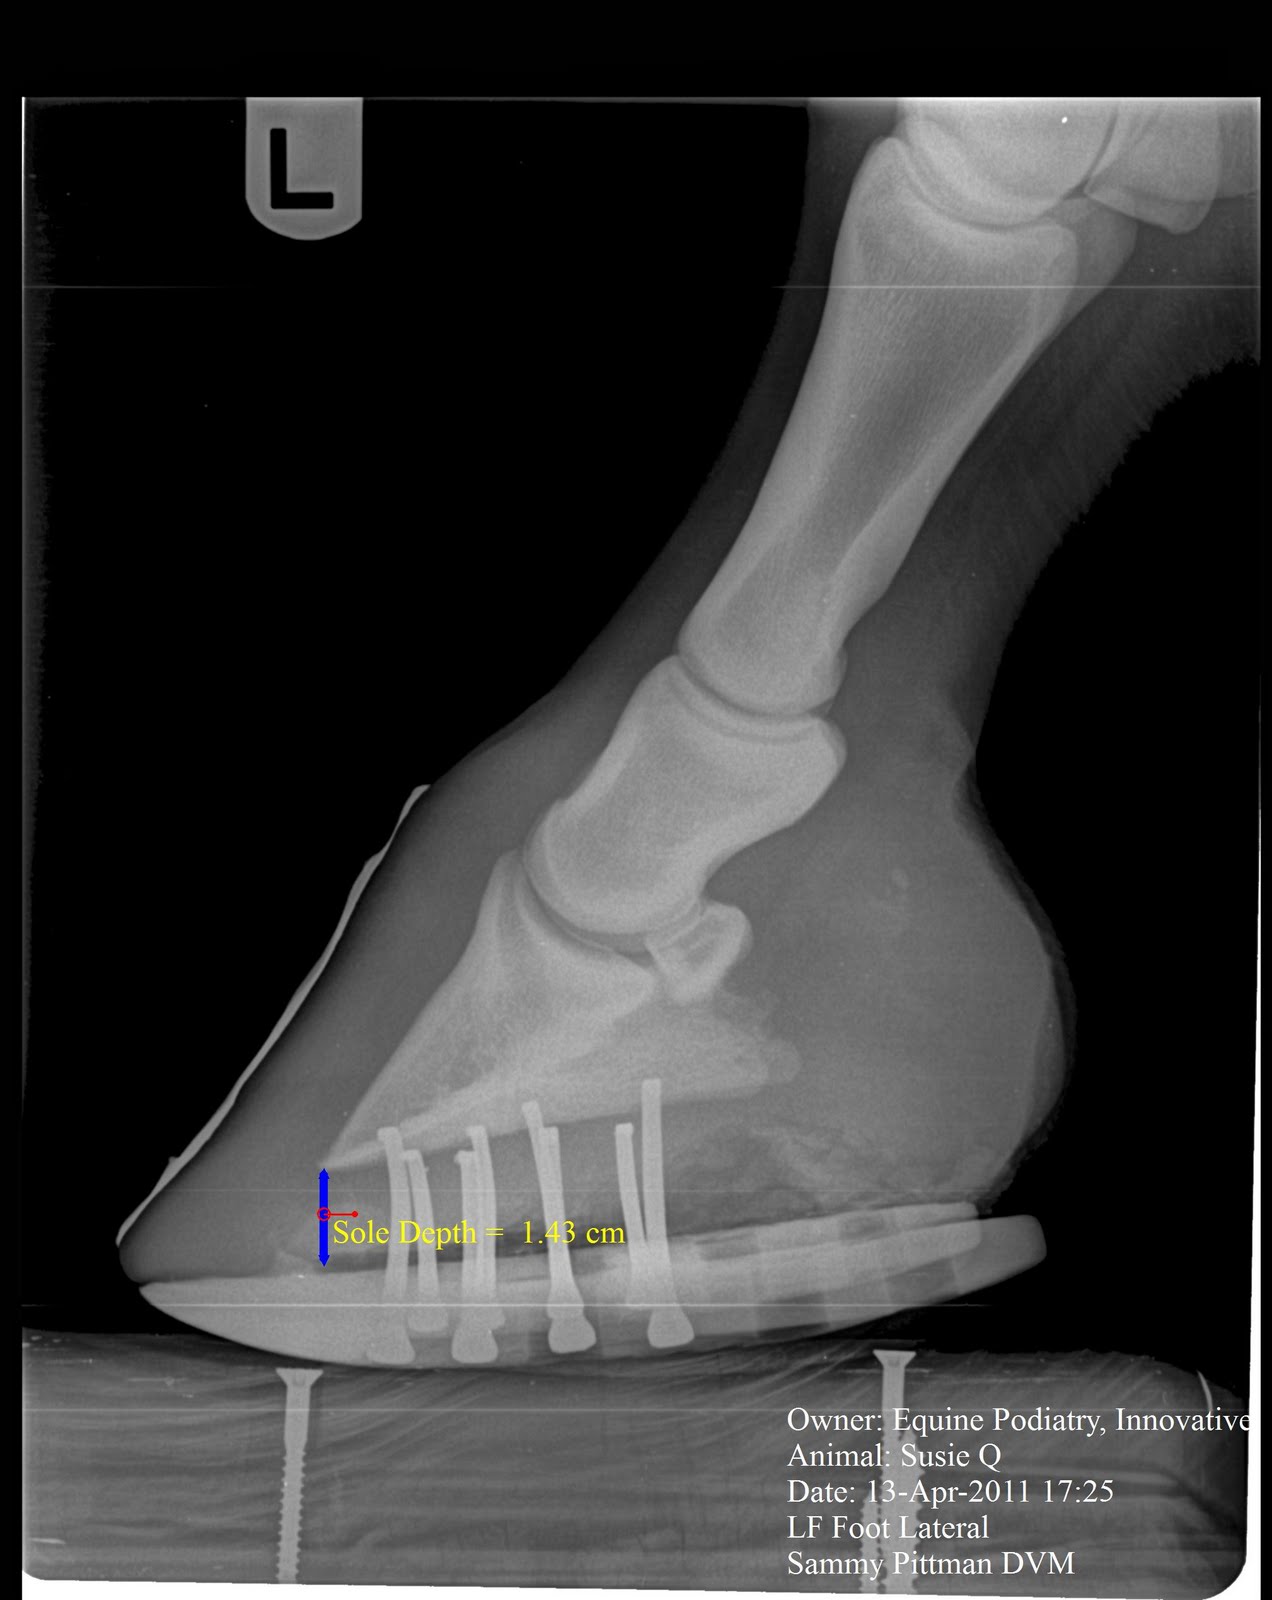

From innovativeequinepodiatry.blogspot.com

Innovative Equine Podiatry Follow up Venograms and Radiographs of the Equine Foot Balance X Rays A balanced foot is functionally efficient and capable of accommodating the basic purposes of the foot; Positioning and selection of exposure factors are of central importance if one. Indications to radiographic the foot include lameness that localized to the region, farriery, regions wounds/lacerations, draining tracts,. Radiographic examination of the equine foot can provide the veterinarian and farrier with a wealth. Equine Foot Balance X Rays.

Innovative Equine Podiatry Radiographic parameters measurement guide Equine Foot Balance X Rays Positioning and selection of exposure factors are of central importance if one. From baseline images to diagnosing complex cases, here’s why x rays should be key components of your horse’s hoof care plan. Indications to radiographic the foot include lameness that localized to the region, farriery, regions wounds/lacerations, draining tracts,. Current radiographic techniques applied to the equine foot allow more. Equine Foot Balance X Rays.